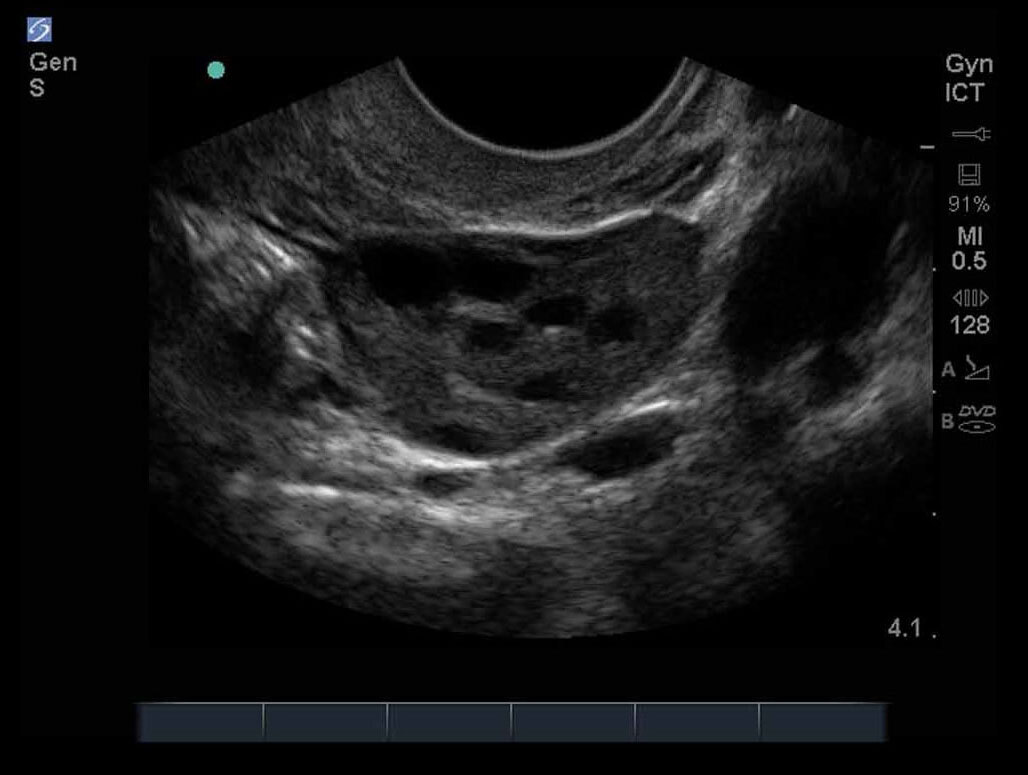

女性の骨盤07画像

M-Turbo:ICT 卵巣1。